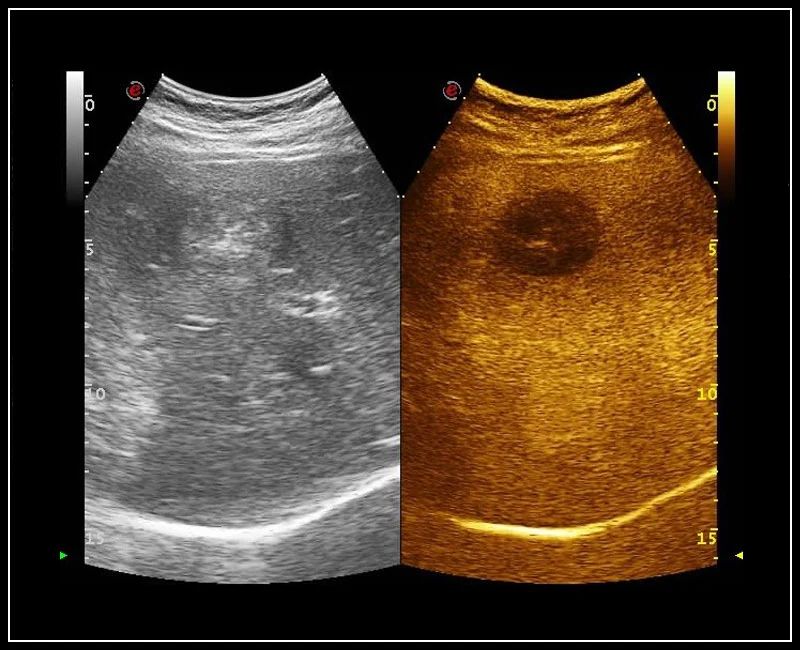

MyLab™E80 - CEUS - Liver

MyLab™E80 - CEUS - Liver